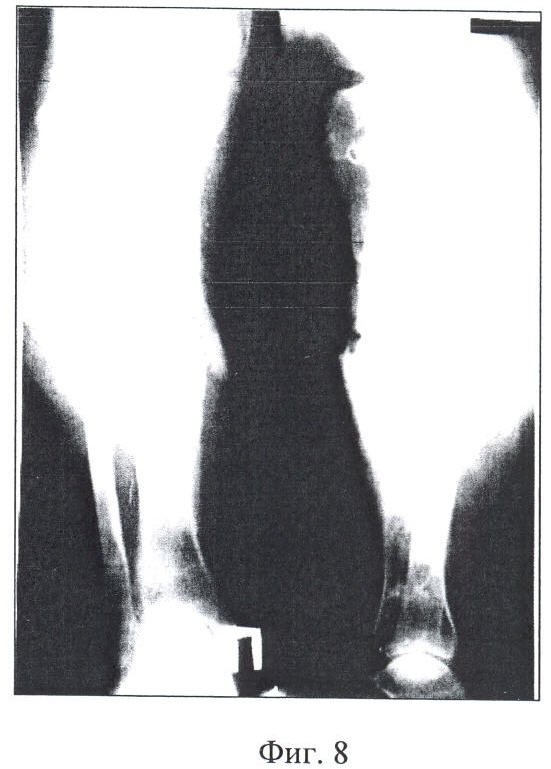

19.12.90 г. после проведенной клинической пробы и рентгенологического контроля был снят КДА Г.А.Илизарова с правой голени, так как наступило сращение перелома костей (фиг.8).

Опороспособная функция конечности восстановлена. Укорочение конечности в значительной степени ликвидировано за счет ортопедической обуви. Выписан из госпиталя. Признан негодным к военной службе с исключением с воинского учета (фиг.9).